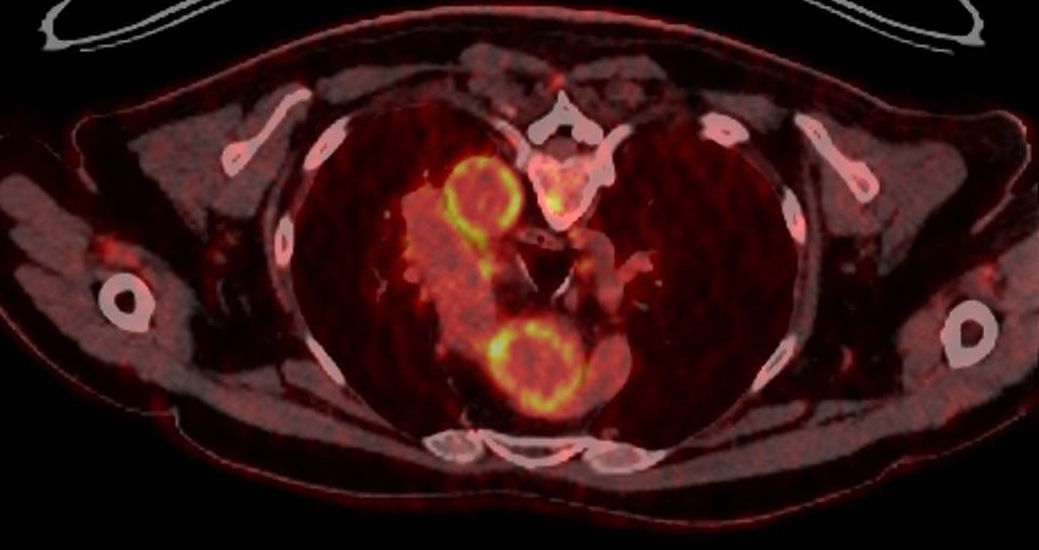

Recherche d’aortite ou d’autre hypermétabolisme orientant la prise en charge.

Vous prescrivez un TEP-scan au 18FDG dont la coupe ci-dessous.

Figure (Étienne Crickx, La Revue du Praticien)

Question 5 - Vous constatez (une ou plusieurs réponses possibles) :

L’aspect est celui d’une aortite avec hypermétabolisme des parois de l’aorte ascendante et descendante.

Devant l’âge de la patiente, les céphalées, le syndrome inflammatoire biologique, et l’aspect de vascularite des gros vaisseaux, vous portez un diagnostic d’ACG. La patiente n’a pas de signes visuels.